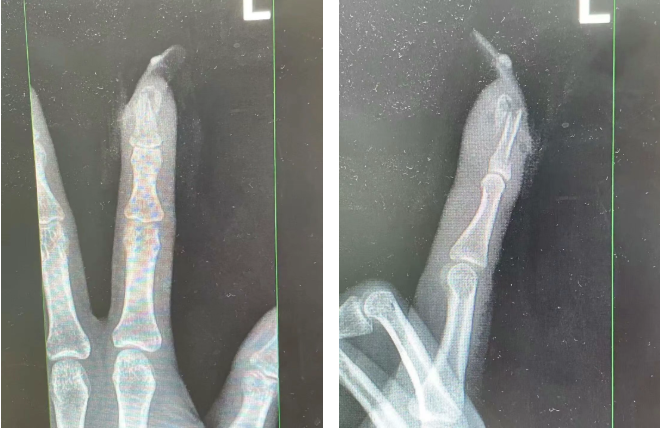

王女士受伤手指的X光影像。图源:杭州市临平区中西医结合医院

经医生检查判断

王女士左手食指指骨骨折

甲床破裂

部分甲床外露

医生表示如果没有美甲

伤害不会这么严重